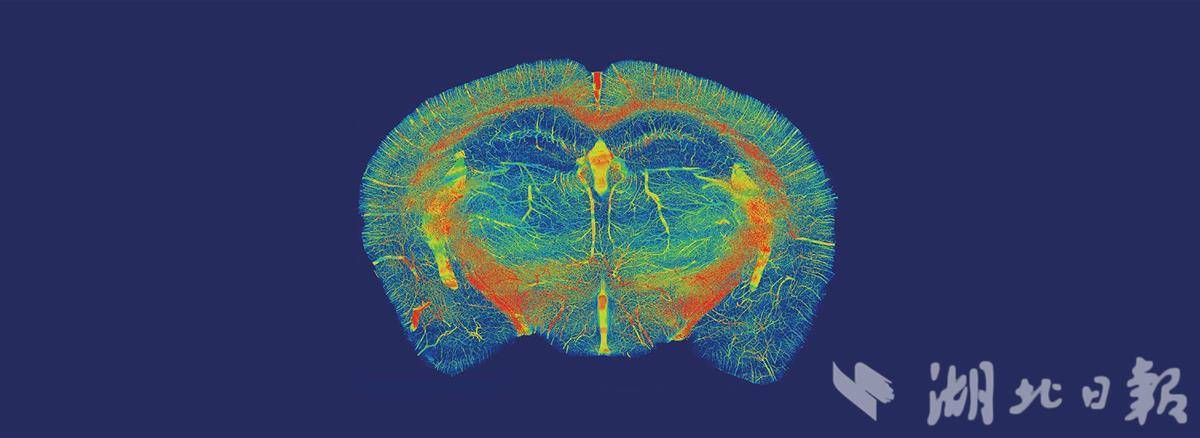

要实现通过脑机接口治疗疾病,首先必须读懂大脑。武汉沃亿生物则致力于绘制大脑三维图谱。

“我们基于MOST(显微光学切片断层成像系统)技术自主研发的设备,可对多种生物的大脑进行精细三维成像,比如小鼠、猪、猴等。”展会上,武汉沃亿生物产品经理陈晓杰说。

举个例子,花生粒大小的鼠脑组织,被快速切削成1微米的薄片,并“拍片”成像。最后,一万多张图像数据叠加,构建出完整的鼠脑三维结构模型。

“通过不断改进,MOST设备已实现组织切片、光学成像、图像配准等全自动化,可以对完整大块组织样品进行高质量数据采集、信息描绘和统计分析。”陈晓杰表示,该技术世界领先,目前已服务国内外100多家科研院所及医院,为脑机接口的研究与应用奠定了坚实基础。

小鼠脑血管高分辨图谱